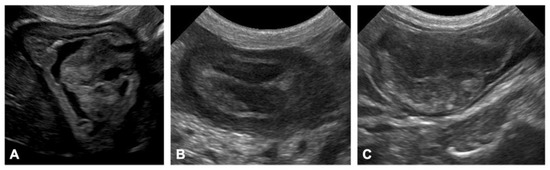

Ultrasonography

CT Scan